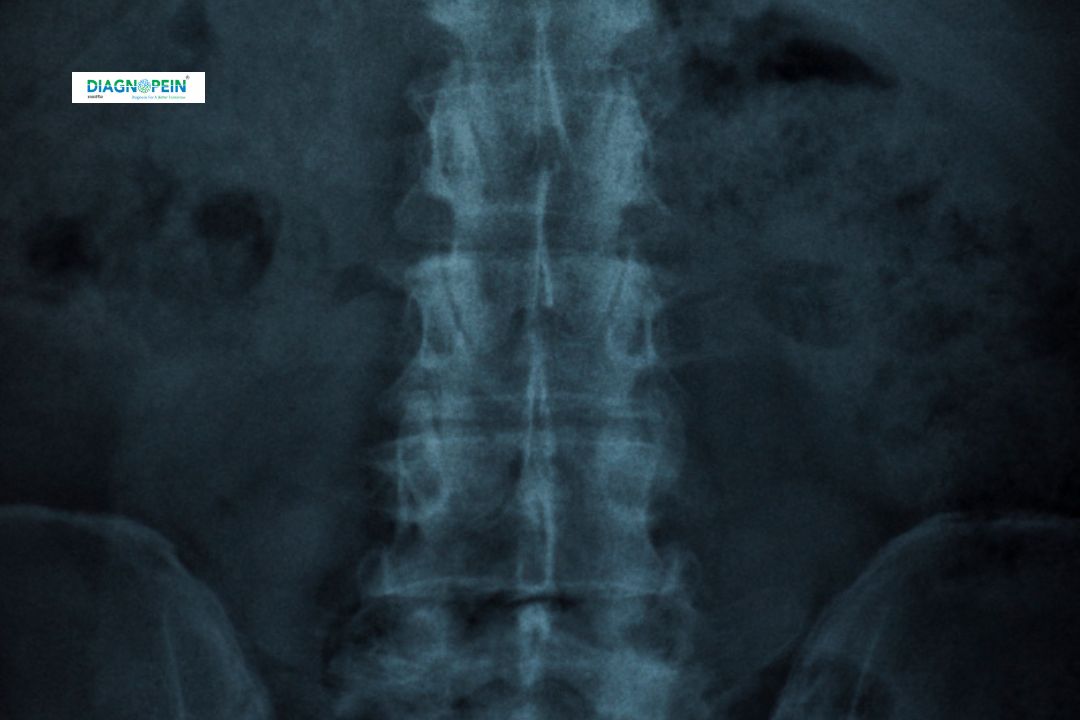

The X-Ray (Barium Enema) is an important diagnostic imaging test used to visualize the large intestine (colon and rectum). It helps doctors detect structural abnormalities, blockages, tumors, ulcers, or other intestinal conditions. In this procedure, a contrast agent called barium sulfate is introduced into the rectum. The barium coats the lining of the colon, making it visible on X-ray images and providing a clear outline of the digestive tract.

3. Imaging: Once the colon is coated, the radiologist takes multiple X-ray images from different angles. The barium outlines the intestine’s shape and reveals any abnormalities.